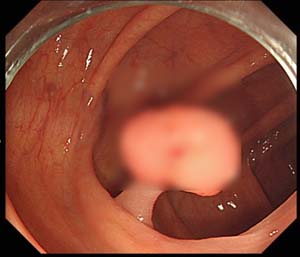

대장 용종

선종성 용종은 대장에 생기는 혹으로 대다수 의 대장암은 원인에 문제될 것 없이 선종성 용종이라고 부르는 암의 전 스탭를 거쳐 암으로 발전하게 되겠습니다. 선종성 용종은 증상이 없는 50세 이상의 성인이 대장 내시경을 하게 되었다면 약 30% 정도에서 발견되겠습니다.

선종성 용종이 얼마나 암으로 발달할 위험이 있는지는 용종의 크기와 현미경적 조직 생각에 따라 격차가 있어요. 범위가 1cm보다 작은 경우는 암세포가 들어 있을 확률이 1% 정도이지만 2cm보다 크면 암세포가 들어 있을 확률이 약 35~50%나 되겠습니다. 또한 조직검사에서 융모성 성분을 충분히 내포하고 있을 경우 암으로 추진할 가능성이 높아지고요.